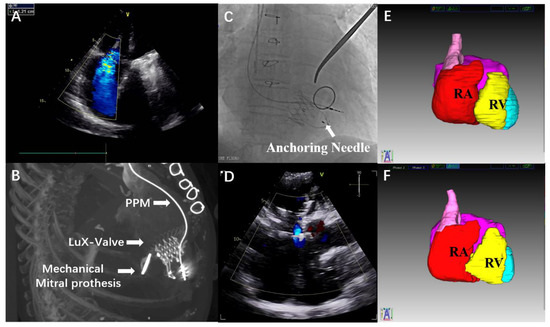

4-Year Follow-Up after Transatrial Transcatheter Tricuspid Valve Replacement with the LuX-Valve

2. Case Report